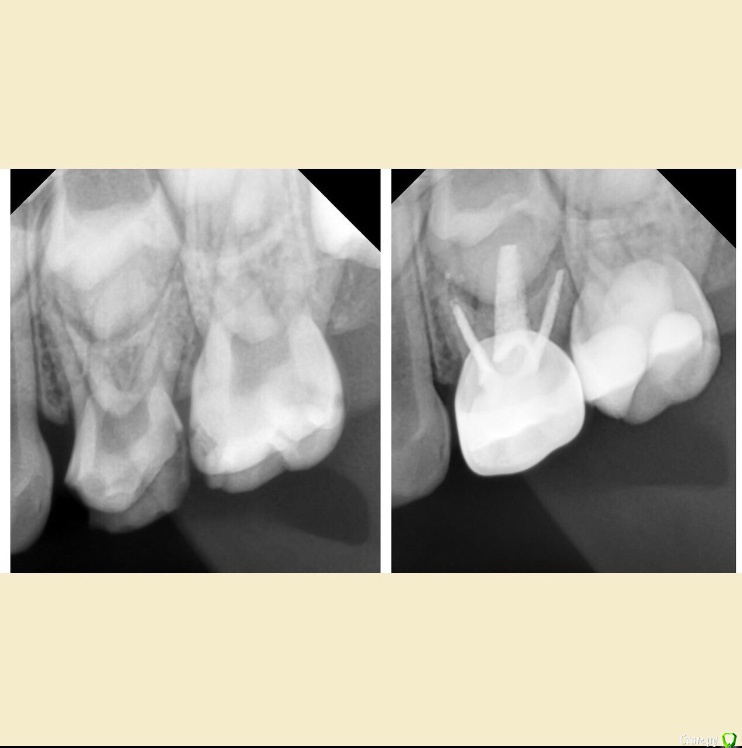

CRAZYDUCK Опубликовано 3 мая, 2018 Автор Поделиться Опубликовано 3 мая, 2018 Просто кариесули 7.4 и 7.5Обязательно убираем миловидную эмаль по контактам ( красной стрелкой на 7.5 указала )Обратите внимание , что rvg практически не визуализирует кариес медиально на 7.5 6 Ссылка на комментарий

CRAZYDUCK Опубликовано 7 мая, 2018 Автор Поделиться Опубликовано 7 мая, 2018 (изменено) Лечение пульпита ; 6.4 необратимый , 6.5 обратимый .Продолжительность 1:15 час ( с момента входа в кабинет и до прощания )6.4-каналы -протейпер дентсплай Sx, ручные инструменты 25.02, гипохлорит 3,2%, пломбирование каналов Йодотин( отличный аналог метапекса , который всегда идёт из канюли в отличии от метапекса ), восстановление культи СИЦ, коронка 3М ESPE стальная .6.5 - ампутация , ХГ2%, спонтанный гемостаз , рутдент быстротвердеющий ( МТА), изоляция Calcimol, реставрация Charisma. Все лечение в одно посещение - долго для ребёнка 4 лет , но так лучше . Пришла к такому методу работы относительно недавно .Больше нравится работать таким образом - 2-3 рядом стоящих зуба в одно посещение . В этот раз было уже не до фото . Для начинающих коллег на rvg выделила полости кариозные и пульпарные полости. Изменено 7 мая, 2018 пользователем CRAZYDUCK 4 Ссылка на комментарий